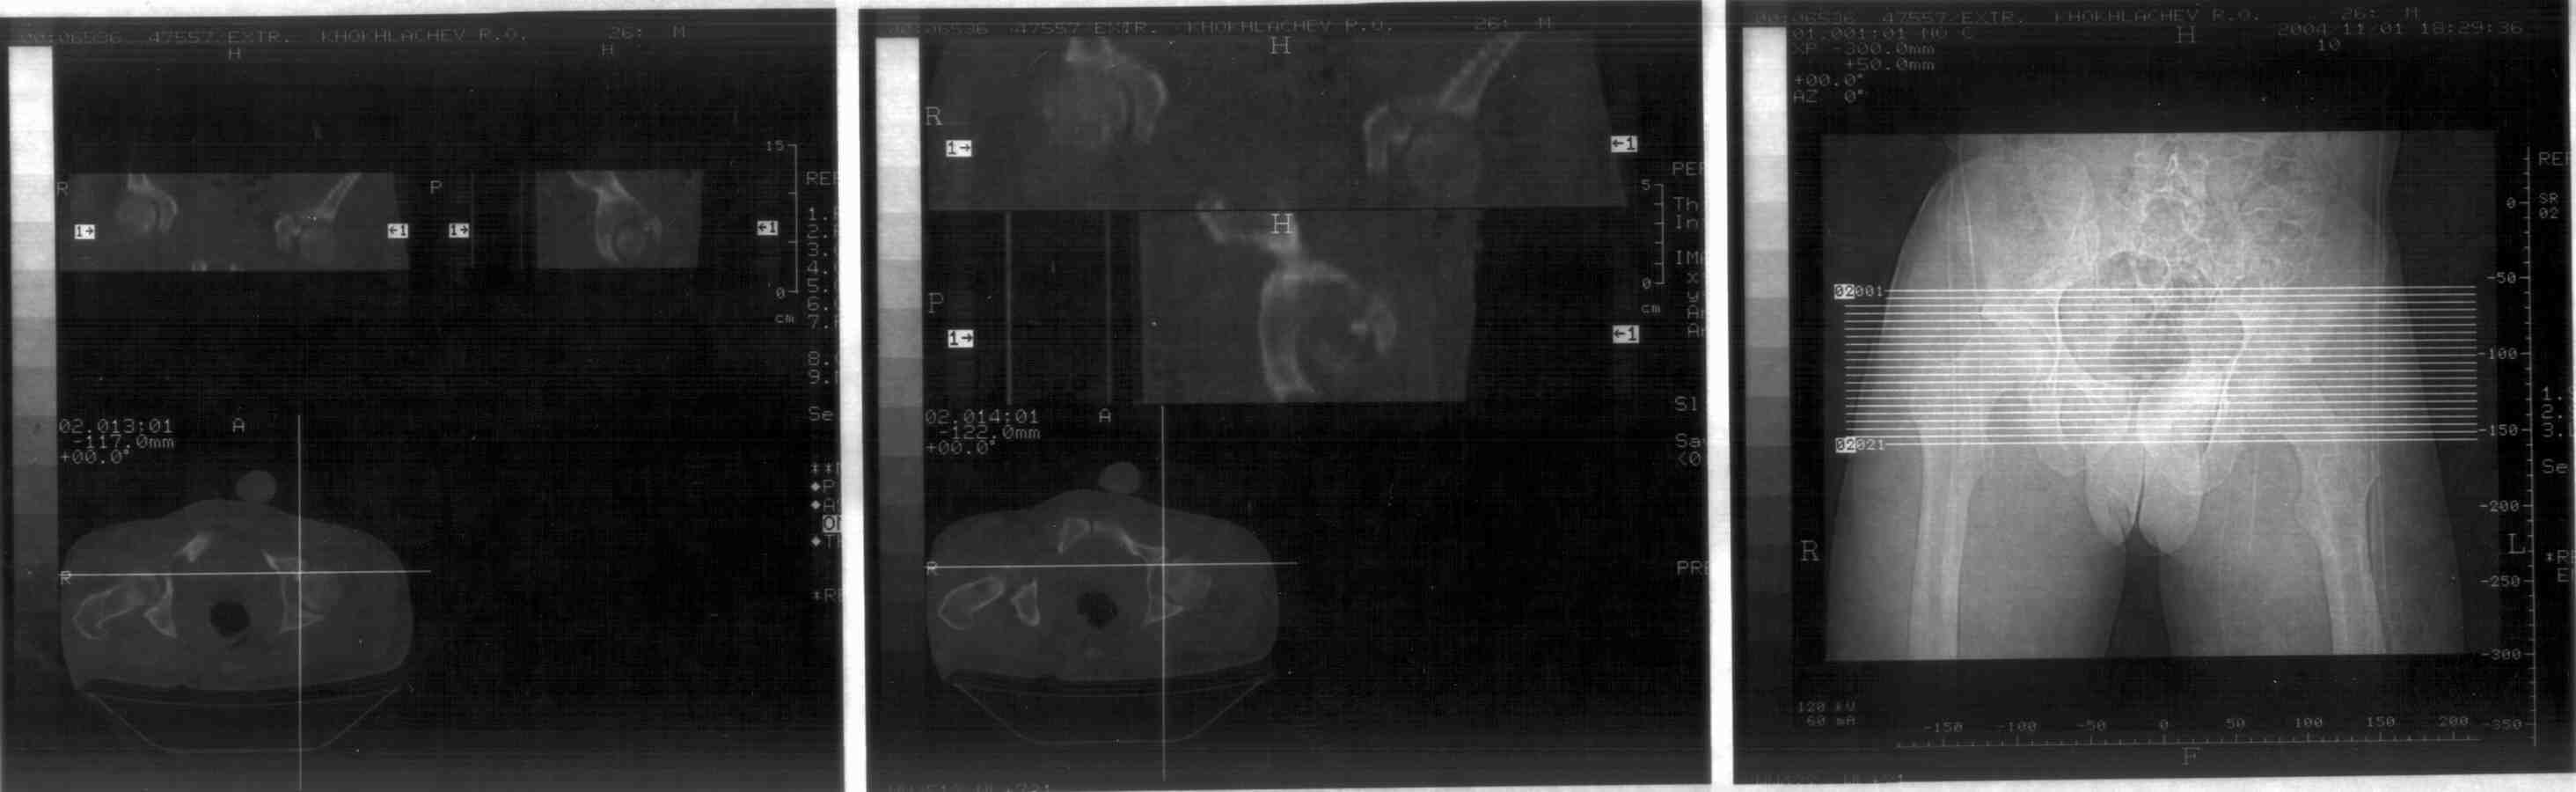

Уважаемые специалисты, 1 октября 26 летний мужчина, получил травму упав на параплане.Диагноз: перелом вертлужной впадины с вправленным подвывихом бедра. В суставной полости есть осколок 15 * 7 мм. В настоящее время проходит лечение на скелетной вытяжке (6 недель).Вопрос: есть ли необходимость в операции по извлечению осколка из суставной полости?

• Кликните для загрузки файла r3.jpg

Диагноз представлен в несколько поверхностной форме. Переломы вертлужной впадины подразделяются на множество разновидностей, и показания к операции определяются далеко не только наличием свободных вргментов в суставе, что само по себе является показанием к операции. Однако задачи операции не ограничиваются лишь удалением свободных фрагментов, необходимо воссоздание конгруэнтной суставной поверхности.